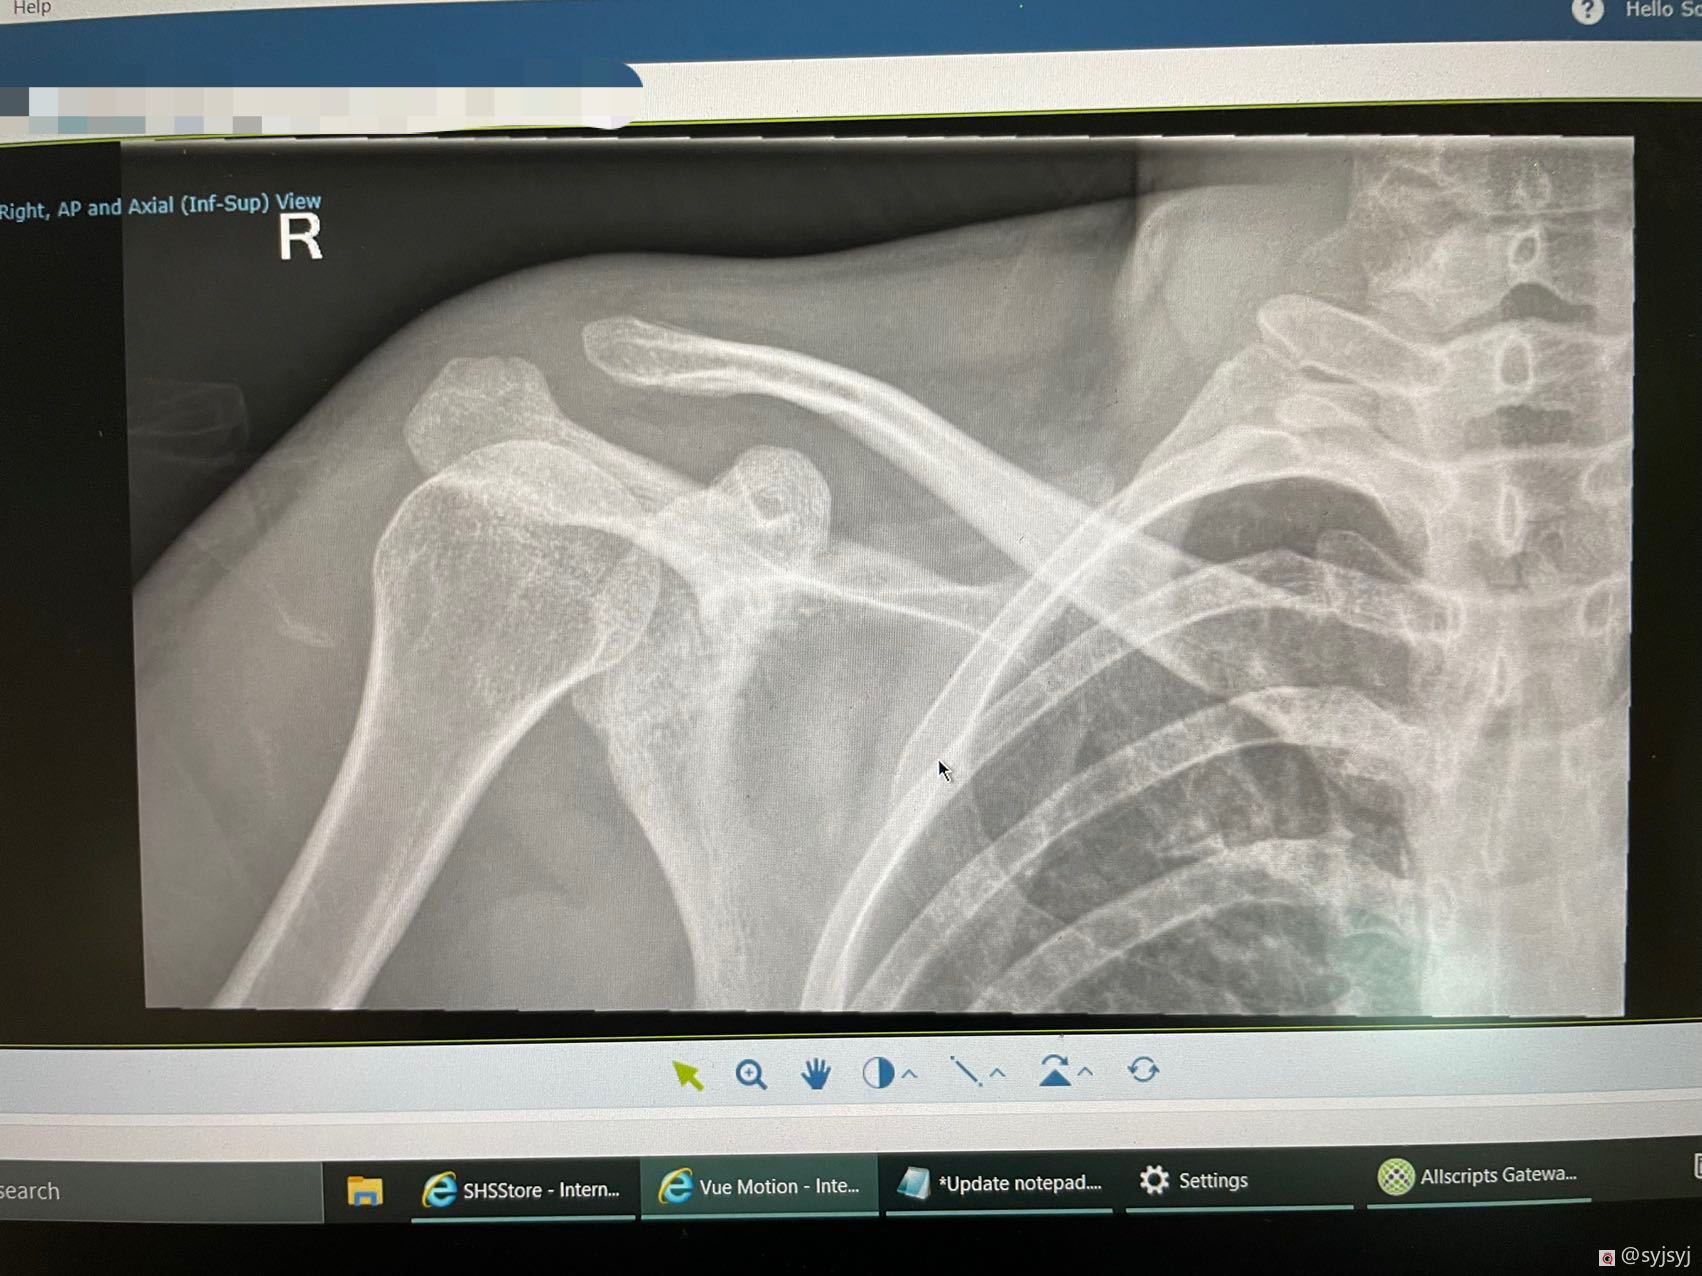

我在1月22号下午遇到了一个摩托车车祸,当时的车速是很快的至少60多码,很不幸的是我飞了出去然后落在了草丛岩石上,当时我是完全不能动弹的,我的右半边身体已经麻木没知觉,除了大面积的擦伤,我的右肩胛骨骨折,手腕背部严重割伤,脊柱第7节压缩。

这些是我伤情的报告:

其实右手臂的伤还不止这些,还有左边也有一些伤,不过右边最严重。